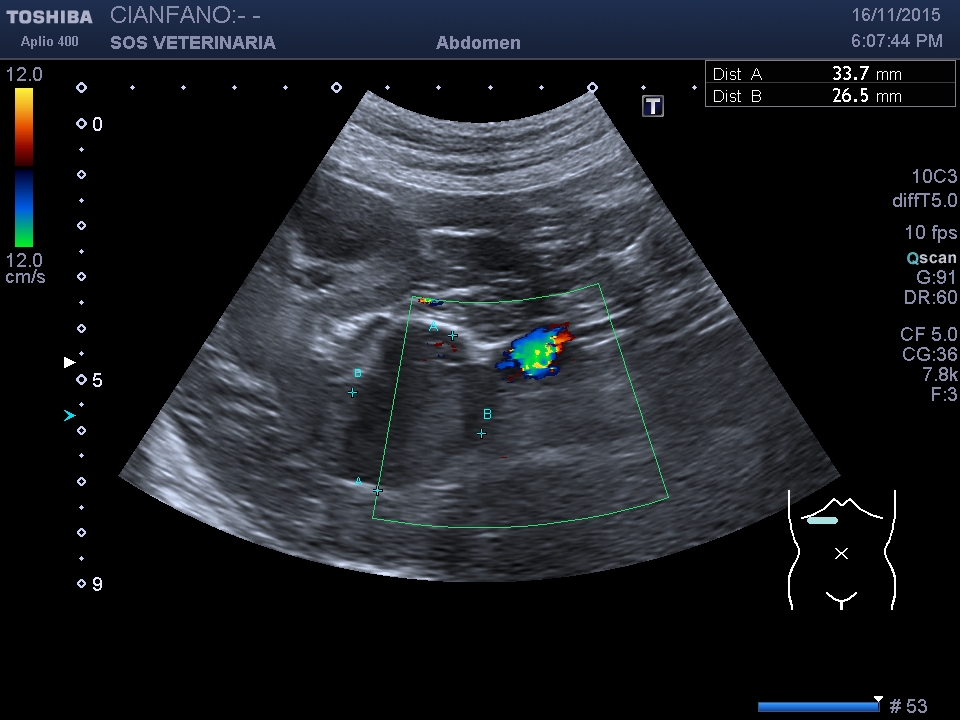

L’invasione cavale puo’ essere di tessuto neoplastico o iniziale formazione di un trombo.

Eseguita ceus e tac

Si conferma l’invasione neoplastica

le informazioni della TAC sono di gran lunga piu’ esaustive della Ceus

Sconsiglio la metodica Ceus per questo tipo di problematiche ,tesorizzare i soldi del cliente con un angio tac che apporta tutte le informazione per le strategie terapeutiche successive.

Il paziente ha avuto effetti collaterali secondari alla somministrazione del contrasto ceus e del contrasto tac (polipnea durata due ore)